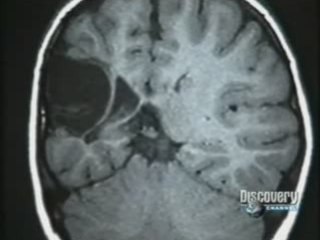

La hemisferectomía es un procedimiento neuroquirúrgico que consiste en la extracción o inhabilitación de un hemisferio cerebral (una de las mitades del cerebro). Este procedimiento es usado para tratar un gran número de trastornos convulsivos donde la fuente de la epilepsia se localiza en una área más o menos amplia de uno de los hemisferios del cerebro. Está únicamente reservada para casos extremos en que las crisis no hayan respondido a los medicamentos u otras cirugías menos invasivas. Todos los pacientes sometidos a hemisferectomías sufren algún nivel de hemiplejia en el lado del cuerpo opuesto a la porción extraída o inhabilitada, y pueden sufrir problemas en su percepción visual. Este tipo de cirugía está casi exclusivamente destinada para que se realice en menores de edad, pues sus cerebros generalmente manifiestan más neuroplasticidad, permitiendo a las neuronas del hemisferio remanente tomar el control de las tareas del hemisferio perdido.